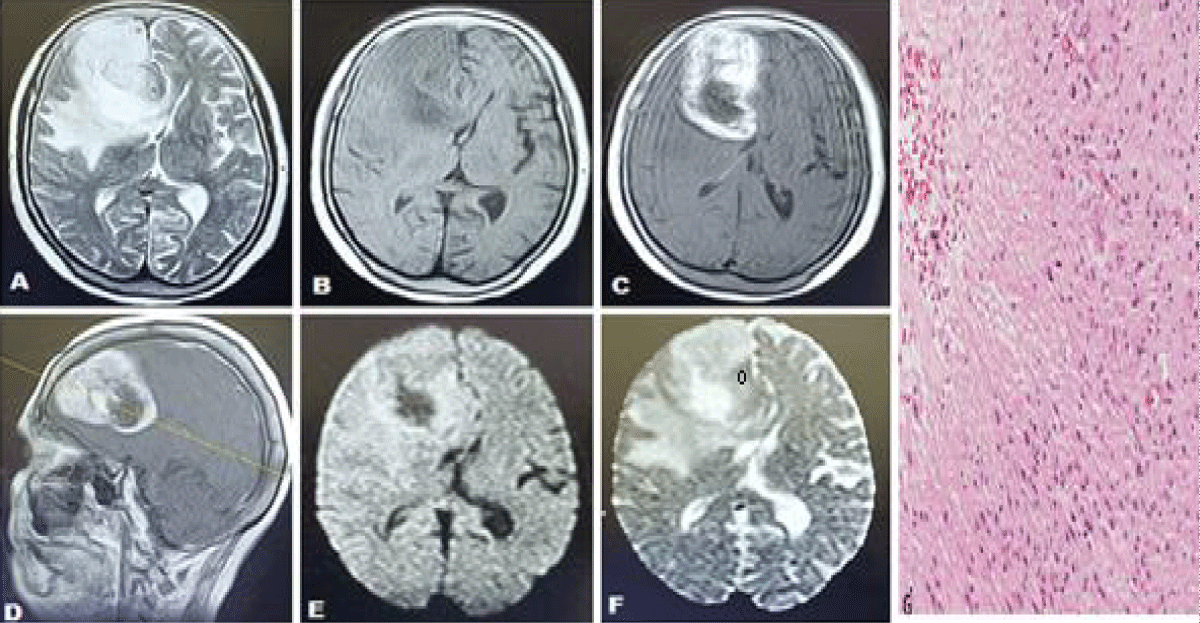

We have conducted this study to determine the diagnostic accuracy of Apparent Diffusion Coefficient (ADC) in differentiating low- and high-grade gliomas, taking histopathology as the gold standard. Overall sensitivity, specificity, positive predictive value, negative predictive value, and diagnostic accuracy of apparent diffusion coefficient (ADC) in differentiating low- and high-grade gliomas, taking histopathology of a brain tumor as the gold standard was 93.65%, 87.64%, 91.47%, 90.70% and 91.16% respectively Figures 3,4.

Figure 3: Case of 56 years old ale presenting with headache and left-sided body weakness (high-grade glioma). Axial T2 weighted sequences (T2WS) (A) axial T1 weighted sequences (T1WS) (B) axial and sagittal post-contrast T1WS (C, D) shows an abnormal signal intensity lesion in the high front temporal lobe extending into genu of the corpus callosum and basal ganglia appearing hypointense on T1WS and hyperintense on T2W sequences with mass effect and edema, demonstrating enhancement on post contrast images (C, D) along with a restriction on Diffusion-weighted images (DWI) (E) and ADC map (F) with a low ADC value of 137 x 10-6 mm2 /sec. (Favoring high-grade glioma). (G) Histopathology showed necrosis and sheets of irregular or elongated cells with pleomorphic nuclei consistent with glioblastoma area.

Figure 4: Case of 44 years female presented with headache and an episode of seizures. Axial T1 weighted sequences (T1WS) (A) and T2 weighted sequences (T2WS) (B) show an abnormal signal intensity lesion in the left frontal lobe appearing hypointense on T1WS and hyperintense on T2W sequences and demonstrating facilitated diffusion on Diffusion-weighted images (DWI) (C) and ADC map (D) with a high ADC value of 1123 x 10-6 mm2 /sec. (demonstrating low-grade glioma). (E) Histopathology report showed scattered microcalcifications which are characteristic of oligodendroglioma.